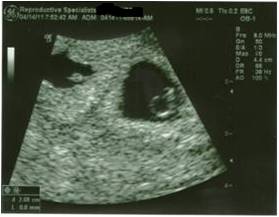

6 weeks 2 day